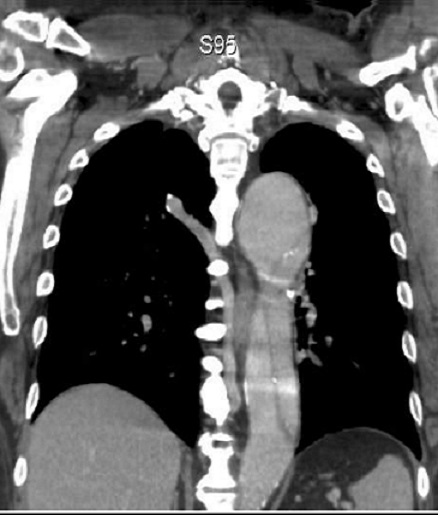

Aspect radiologique de

veine Azygos sur cliche pulmonaire de face

. Le trajet du veine est engager si profonde

dans apexdu poumon et contourne completement

par la plevre parietale et viscerale |

Meme

cas en coupe TDM axiale à travers D3 , apex du

poumon . La scissure Azygos etre en vue comme

une bande hyperdensite du pomon droit . Image

radiologique TDM en coupe axiale , fenetre

mediastinale |